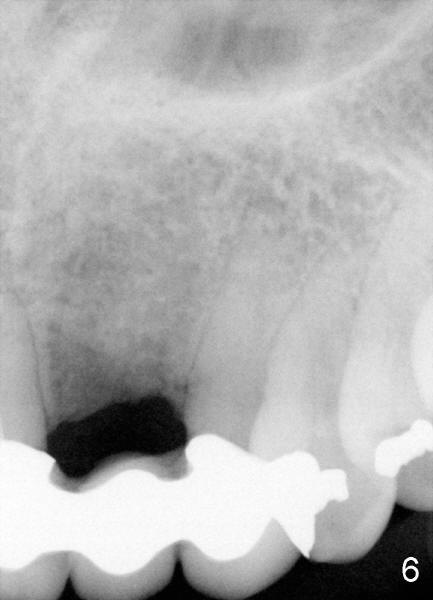

Segmental Osteotomy for Misplaced Implant

This corrective surgery was performed by Dr. Bernee Dunson.

Xin Wei, DDS, PhD, MS 1st edition 12/21/2011, last revision 12/23/2011